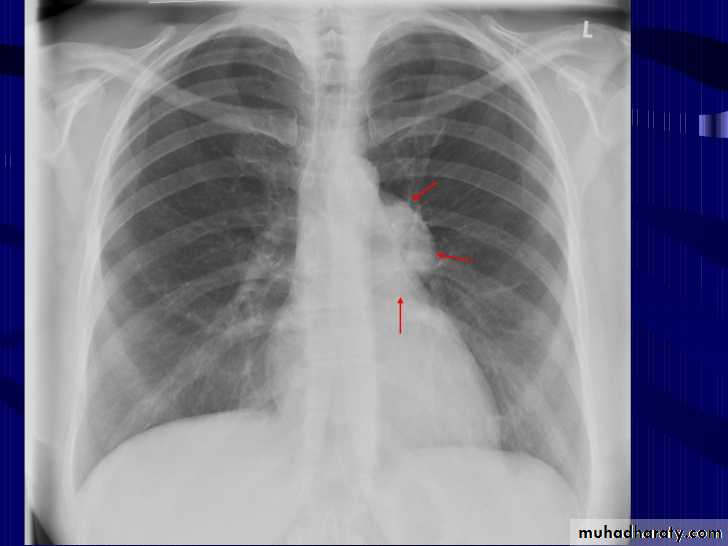

Hodgkin lymphoma of te middle mediastinum

Signs of enlarged bronchopulmonary lymph nodes or hilar mass on frontal chest radiographs include : hilar enlargement, increased hilar density, lobulation of the hilar contour, and distortion of central bronchi . An abnormal hilum is most easily appreciated by comparison with the contralateral hilum and by review of prior chest radiographs . An increase in density of the hilar shadow is seen with a hilar mass that lies primarily anterior or posterior to the normal hilar vascular shadows. In such patients, the enlarged hilar nodes will produce an increase in density on frontal views and a lobulated appearance when viewed in profile on a lateral radiograph.When an abnormally dense hilum is noted, the relationship between the vessels and the density must be assessed. A density through which the normal hilar vessels can be seen constitutes a hilum overlay sign, which indicates a mass superimposed on the hilum.